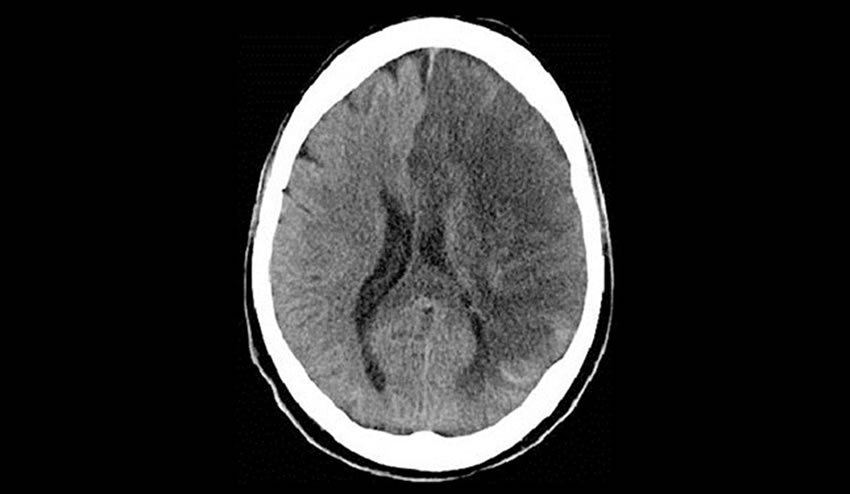

Arritmias cardiacas y embolias

La parte oscura que se observa en el cerebro es a la que le falta irrigación. Cuando la embolia obstruye el flujo del lado derecho del cerebro, la parálisis será en la mitad del lado izquierdo del cuerpo y visceversa.